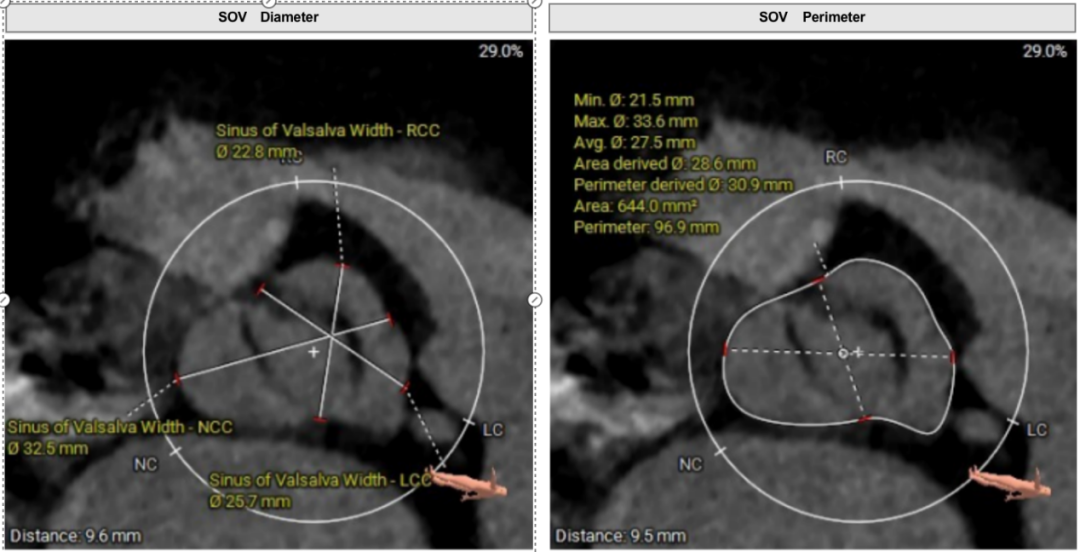

冠脉风险评估

双侧冠脉开口高度良好,瓣叶长度适中,综合瓦氏窦及窦管交界内径,冠脉风险较低。

①Type1二叶瓣,瓣环较小,无窦较大,左右窦有明显瓣叶融合脊;

②瓣叶增厚,瓣口打开受限;

③整体无钙化,AR为主。